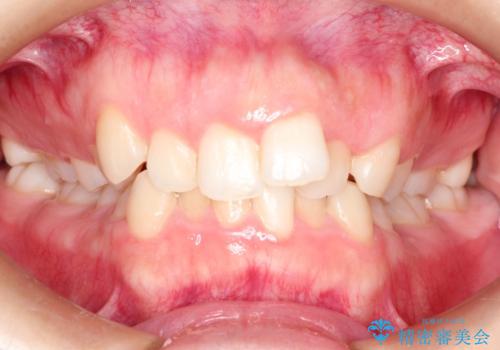

初診時の歯並びの状態としては、上下ともに全体に及ぶの中等度以上のがたつき(叢生)があり、全額的に歯列のアーチが内側に押しつぶされた状態でした。

強い叢生がありましたが、抜歯は行わず上下顎ともに、主に歯列弓の拡大を行い叢生を改善しました。